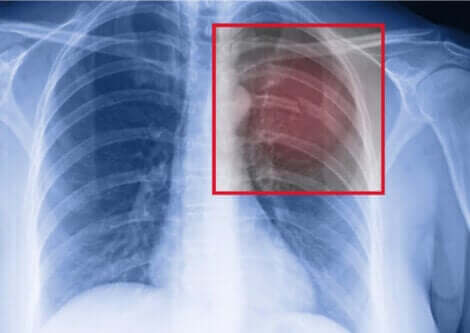

Eğer bir sporcuysanız ve kaburga kırığından müzdaripseniz, yapmanız gereken ilk şey bir doktora danışmaktır. Yaralanmayı doğrulamak için bir göğüs röntgeni yapılacak ve uzantısı değerlendirilecektir.